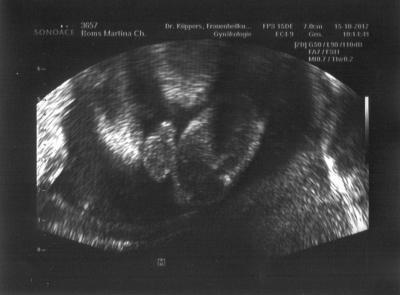

So bin wieder zu Hause. Beim Gyn war alles super. Das erste CTG wurde geschrieben und Felix war gar nicht begeistert. Entwerder hat er gegen getreten oder weggedreht, das der Alarm losging weil die Herztöne nicht mehr da waren. Dann hat der Arzt nach dem Gebärmutterhals geschaut. Alles top. Dabei sahen wir das Felix in mir sitzt und es gab ein eindeutiges Outingbild. Mit Joshua kann ich leider erst morgen zum Doc. Da es beim Gyn lang gedauert hat waren schon alle Termine für heute weg.

Bild zu Guten Abend - Forum für Februar - Mamis

Freut mich, dass bei euch alles gut ist! Und sehr schönes Foto!